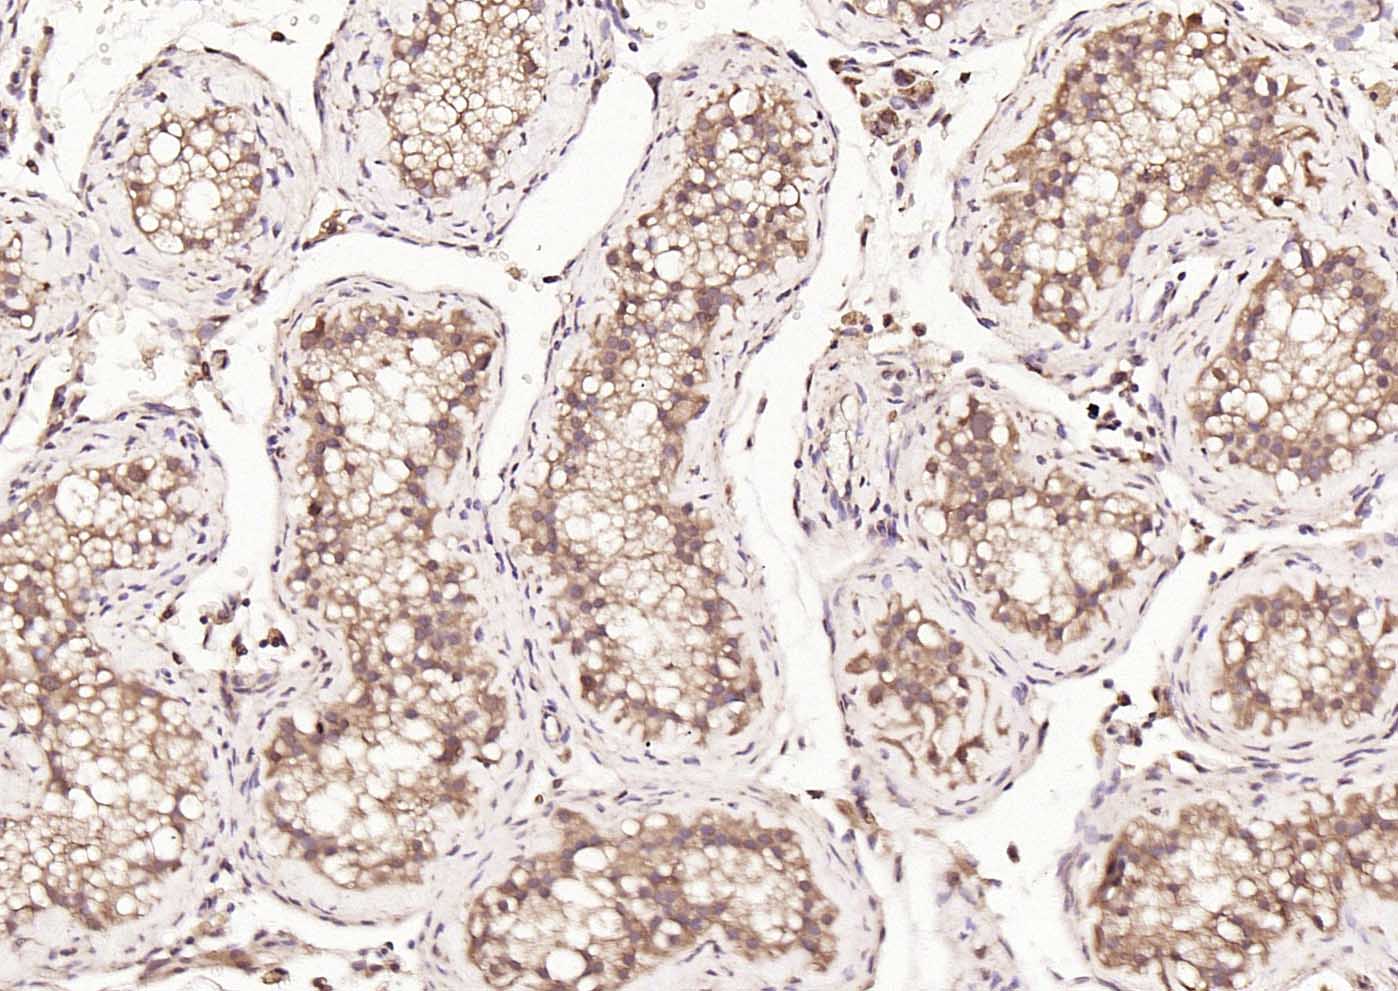

| 英文名称 | HDAC2 Rabbit pAb |

| 中文名称 | 组蛋白去乙酰化酶2抗体 |

| 产品应用 | IHC-P=1:100-500, IHC-F=1:100-500, IF=1:100-500 Not yet tested in other applications. |

| {IHC-P} | {1:100-500} |